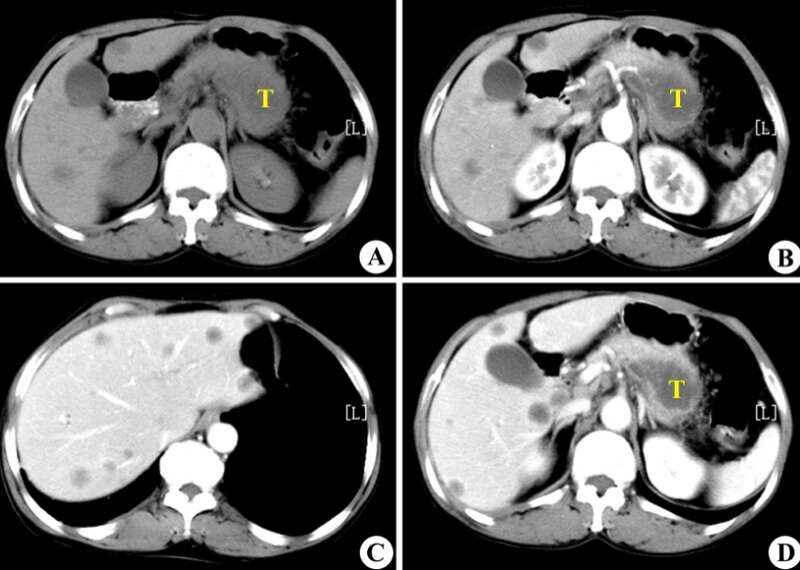

去年4月,本来只是因为一点小咳嗽,去医院做了个常规的CT平扫,没想到这一扫,黄女士竟然被AI识别成了疑似早期胰腺癌。

返回医院复查后,AI的判断果然是对的:胰尾部真的有肿块!

在使用对比剂进行增强扫描后,确定其大小为25×31mm。这大约是一颗中等大小的葡萄那么大。

在前面提到的阿里所使用的PANDA模型中,最重要的一个技术,就是一种叫做“图像配准”的技术,将对比增强CT上的病变标注“复制”到非对比CT图像上。

用直观的语言来描述,这种做法就是:先找两张CT图片,其中一张是普通CT,另一张是增强CT,之后,PANDA通过将两张CT“重叠”在一起的办法,来将增强CT上的病变区域准确地映射到普通CT的相应位置上。

需要说明的是,这里的“重叠”,并不是简单地将两张图片进行物理上的重叠,而是通过算法,识别两张图片中的特征,并计算出它们之间的对应关系。